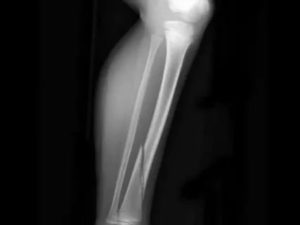

Рентген-снимок перелома малой берцовой кости, смещенного по оси.

Открытые и закрытые переломы

В зависимости от целости кожных покровов разработана еще одна классификация переломов:

- закрытые. При закрытом переломе костные фрагменты не выходят из-под кожных покровов – не образуется открытой раны. Участки кости могут прощупываться непосредственно под кожей, в таком случае ключевой задачей является предупреждение их выхода наружу;

- открытые. Открытый перелом берцовой кости характеризуется повреждением кожи, когда фрагменты кости видны в открытой ране (выпирают наружу). Является тяжелой травмой, которая требует оказания медицинской помощи в кратчайшие сроки. Вероятность развития шока при открытом переломе гораздо выше, чем при закрытом типе.